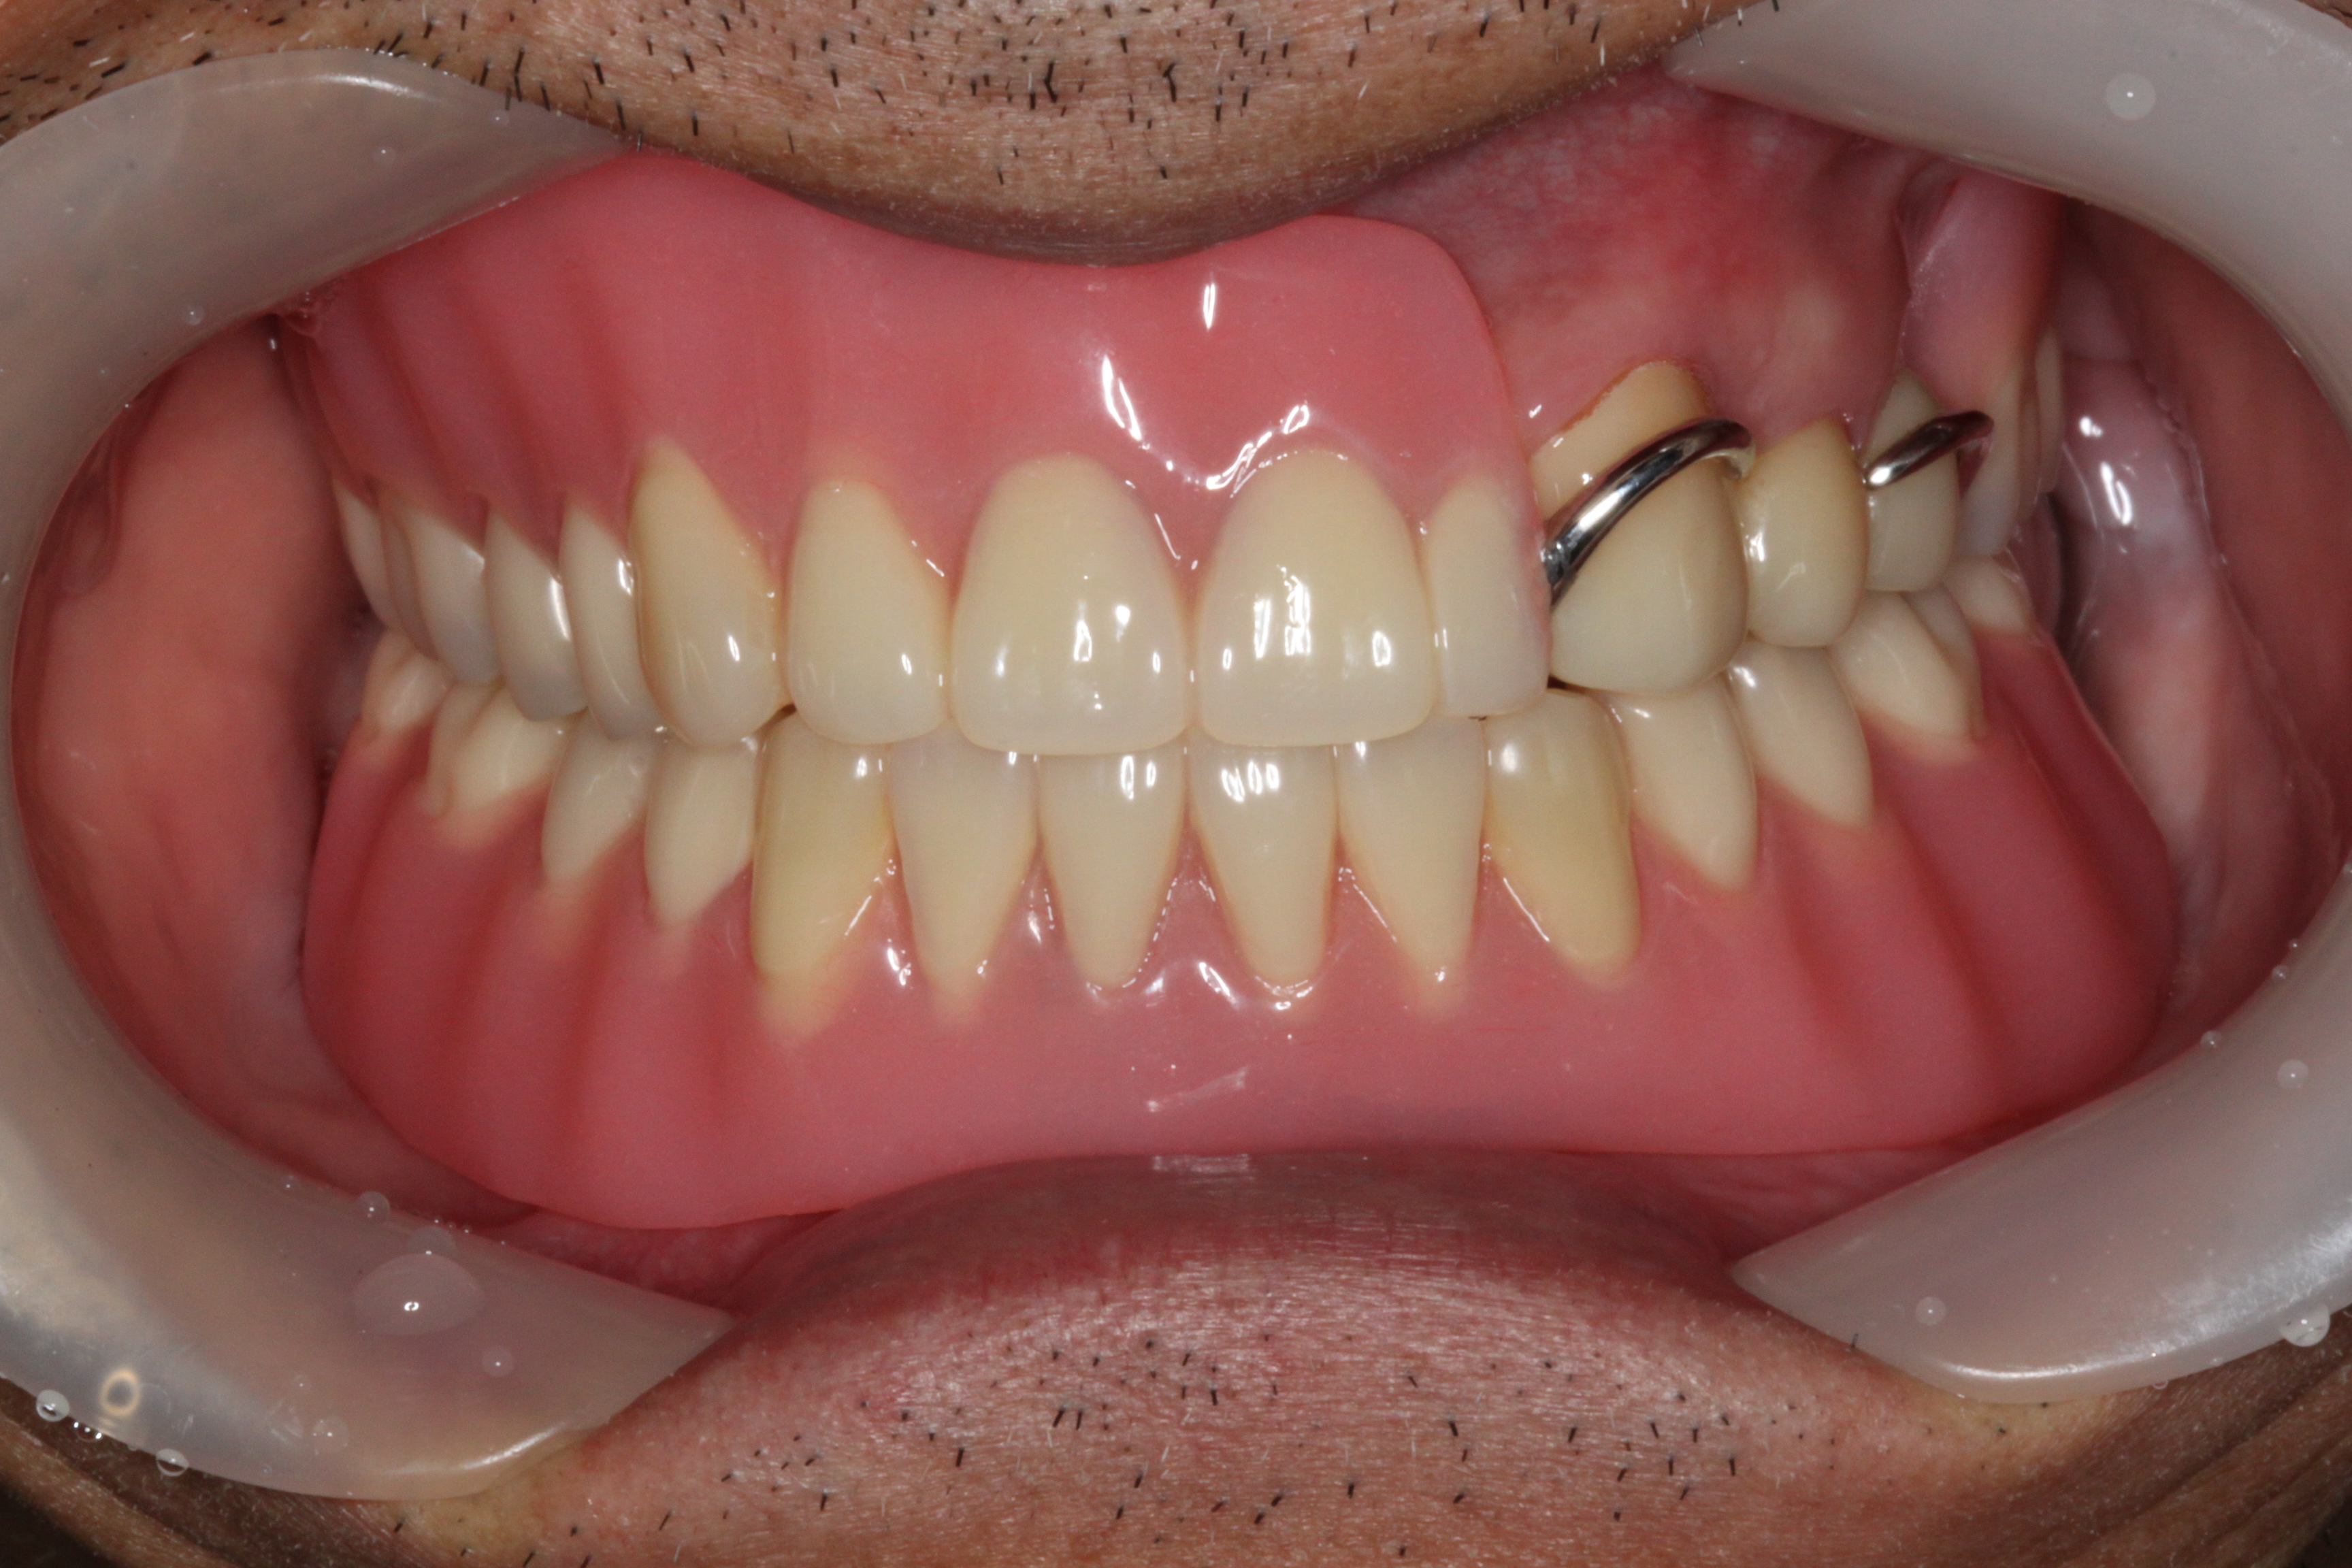

BEFOREAFTERBEFOREAFTER(식립)AFTER(착용)